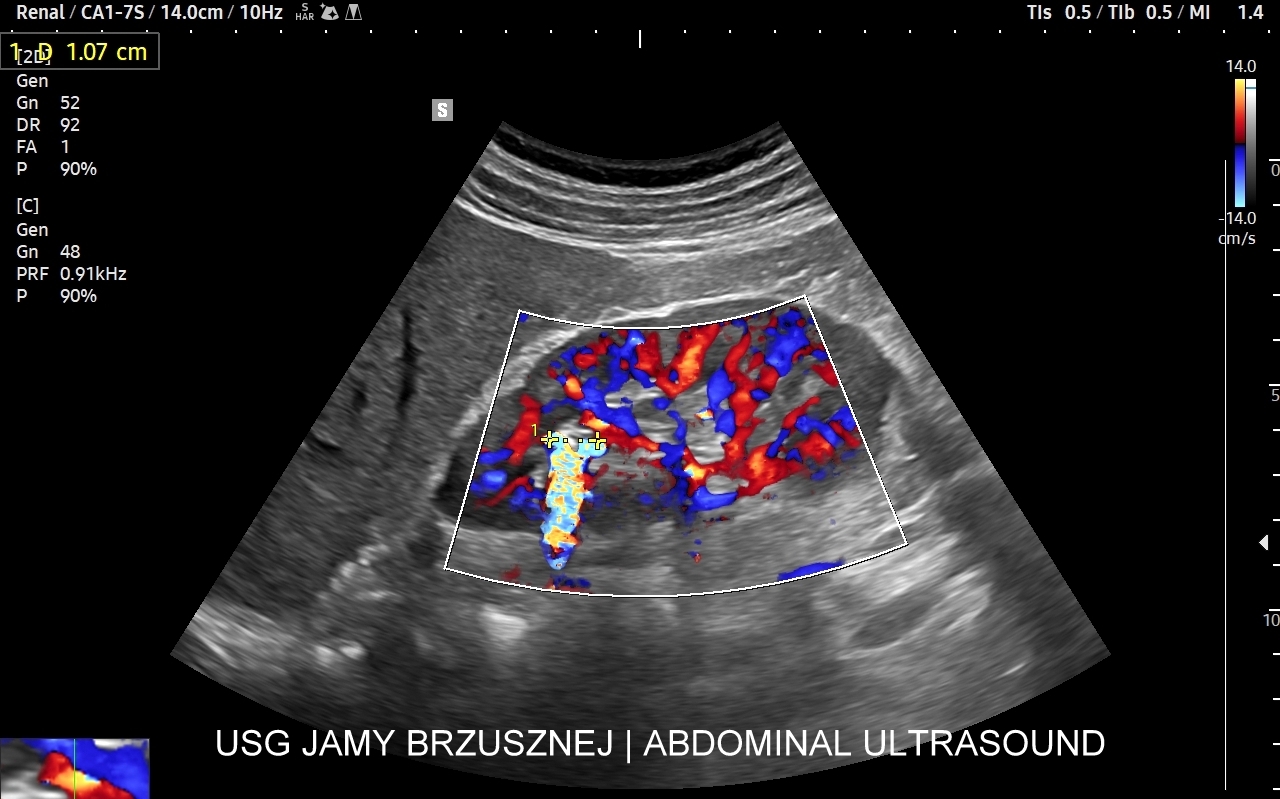

Rozwinięciem standardowego badania USG jamy brzusznej jest badanie multiparametryczne MPUS (ang. multiparametric ultrasound), w ramach którego wykorzystuje się różnorodne, nowoczesne modalności sonograficzne, takie jak tryby mikrounaczynienia MVI, B-flow, elastografię, ilościową ocenę stłuszczenia wątroby QUS, czy tryb Dopplera spektralnego, a to wszystko w celu uzyskania dodatkowej oceny funkcjonalnej i biologicznej struktur, narządów oraz tkanek jamy brzusznej. Obrazowanie MPUS niejednokrotnie poprawia także wizualną ocenę narządów wewnętrznych, czego przykładem jest zastosowanie trybu MVI w ramach bezkontrastowej angiografii sonograficznej naczyń oraz w ocenie guzów nerek. Klasycznymi i najczęstszymi zastosowaniami badania MPUS są jednakże funkcjonalna ocena wątroby w kierunku stłuszczenia, zwłóknienia, zapalenia i nadciśnienia wrotnego, a także ocena żywotności i funkcji nerek.

• Możliwość rozszerzenia zakresu badania USG w razie wystąpienia konieczności. Praktycznymi przykładami są zastosowanie trybu MVI w przypadku wykrycia guzka w nerce, czy przeprowadzenie badania elastograficznego i dopplerowskiego w wypadku stwierdzenia nieprawidłowego obrazu wątroby.